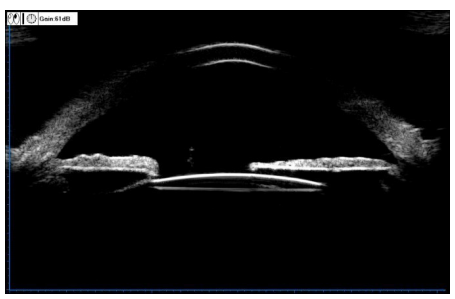

术后经散瞳裂隙灯显微镜检查及UBM检查,所有患眼IOL位置均居中。见图3。

20230223110908_7124.png

图 3 IOL 术后位置居中

Figure 3 The position of IOL was centered